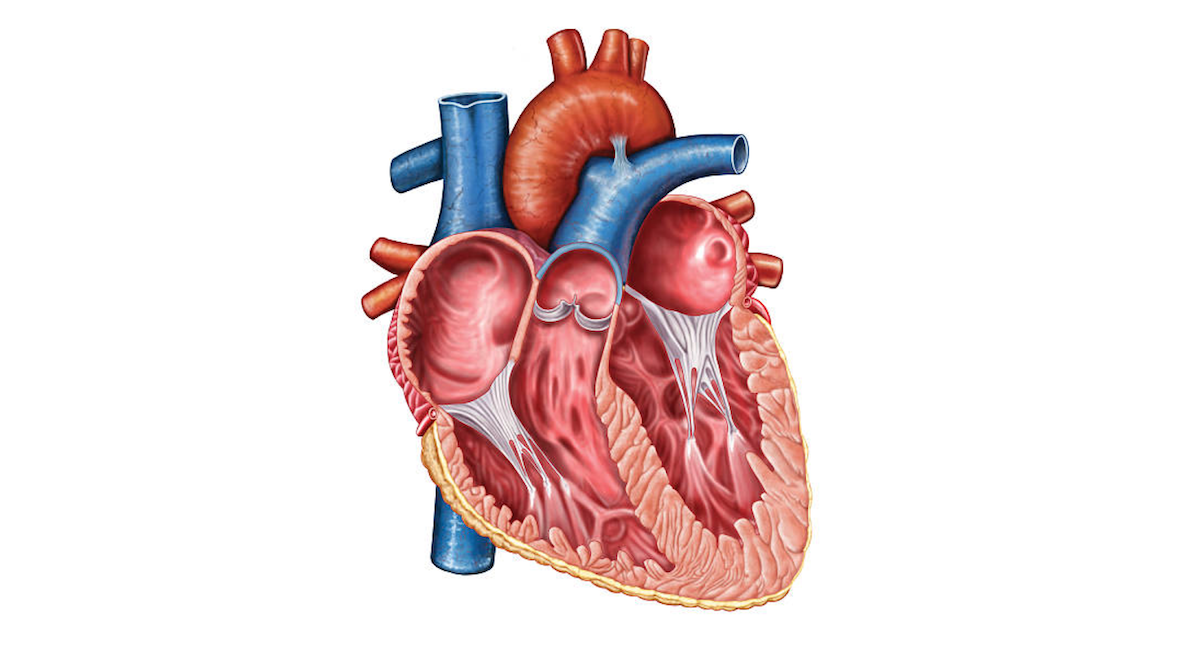

Which vessels supply the myocardium of the heart? Where do these vessels come from? (branches of which artery)

coronary arteries; aorta

What does the chordae tendineae attach to? What is the function of the chordae tendineae?

papillary muscles; prevents prolapse of heart valves

Trace the electrical conducting system of the heart. (name the structures involved in order)

SA, AV, Bundle of His, Purkinje fibers

Name the following valves:

1. Valve between the right ventricle and pulmonary artery

2. Valve between the right atrium and right ventricle

3. Valve between left atrium and left ventricle

4. Valve between left ventricle and aorta

1. Pulmonary semilunar valve

2. Tricuspid valve

3. Mitral (bicuspid) valve

4. Aortic semilunar valve

Which vessel carries deoxygenated blood away from the heart to the lungs? Which vessel carries oxygenated blood from the lungs to the heart? Which vessel carries oxygenated blood from the heart to the systemic circulation?

Pulmonary arteries; pulmonary veins; aorta

Come up and point the pathway of the heart's conducting system from the Atria to the Ventricles.

(Point toward the locations of the four main nodes that are involved)

SA node (Right Atrium)

AV Node (Just above the left side of the Tricuspid valve)

Bundle of His (Located just in the bottom left corner of the right atrium)

Purkinje Fibers (From Apex to the outside cardiac tissue of both ventricles)

How many total openings are typically found in the left atrium, including those for the pulmonary veins and the mitral valve?

The left atrium usually has four openings for the pulmonary veins (two from each lung) and one opening for the mitral valve, totaling five openings.